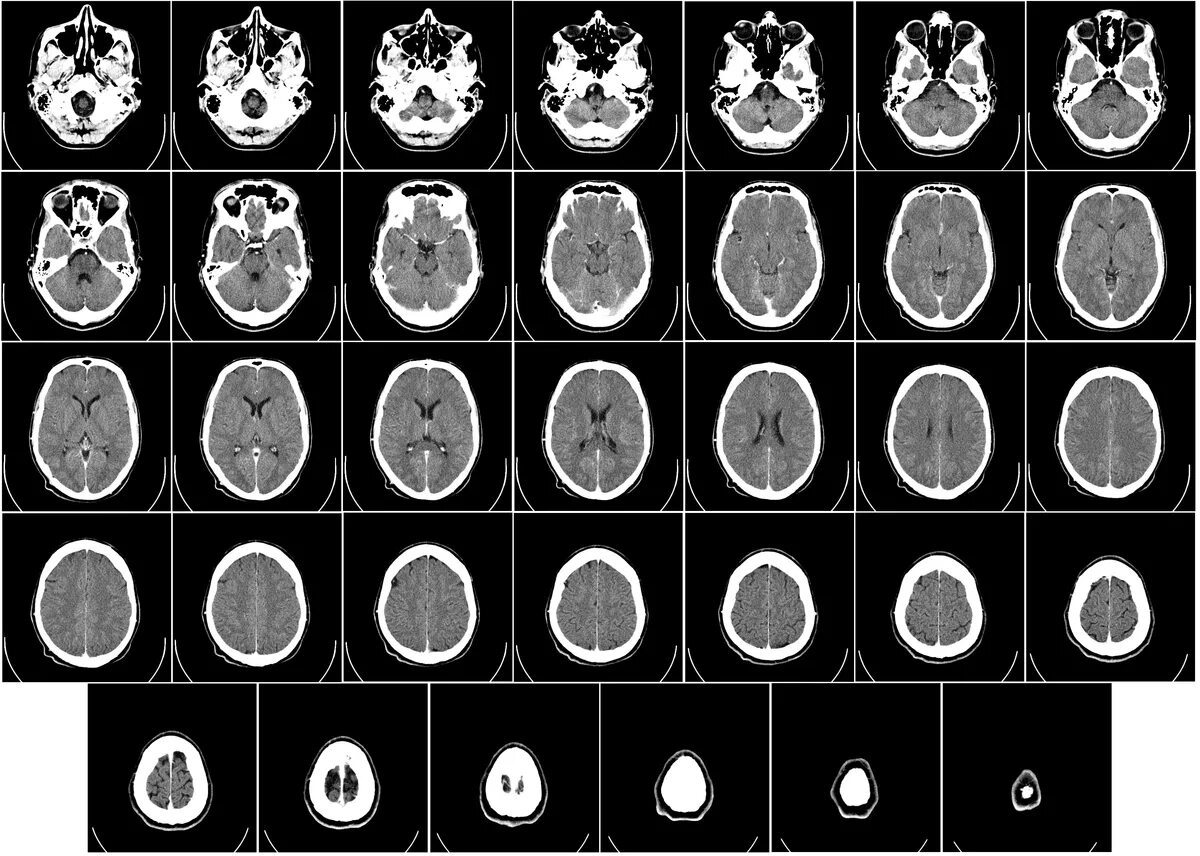

Какие виды кт